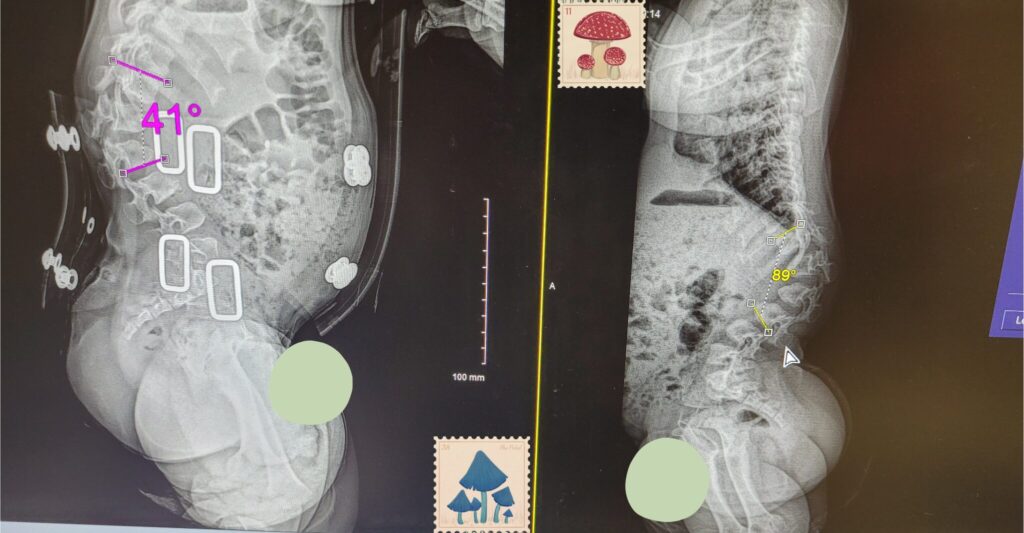

2歳0か月 初代コルセット

コルセットなし 73度 → コルセット有り 54度

2歳10か月 2代目コルセット

コルセットなし 89度 → コルセット有り 41度

まさかの悪化していました…正直衝撃過ぎて…2歳で歩行できなかったモーリーが2歳6か月で歩き始めたのもあって少しは改善しているのでは?と期待していたので落ち込みました。ちなみにモーリーは上記にあげた、赤ちゃんの時にやってはいけないことは避けて予防してきました。子供3人いるのでどうしても縦抱き抱っこをしなくてはいけない時が度々あったくらいです。